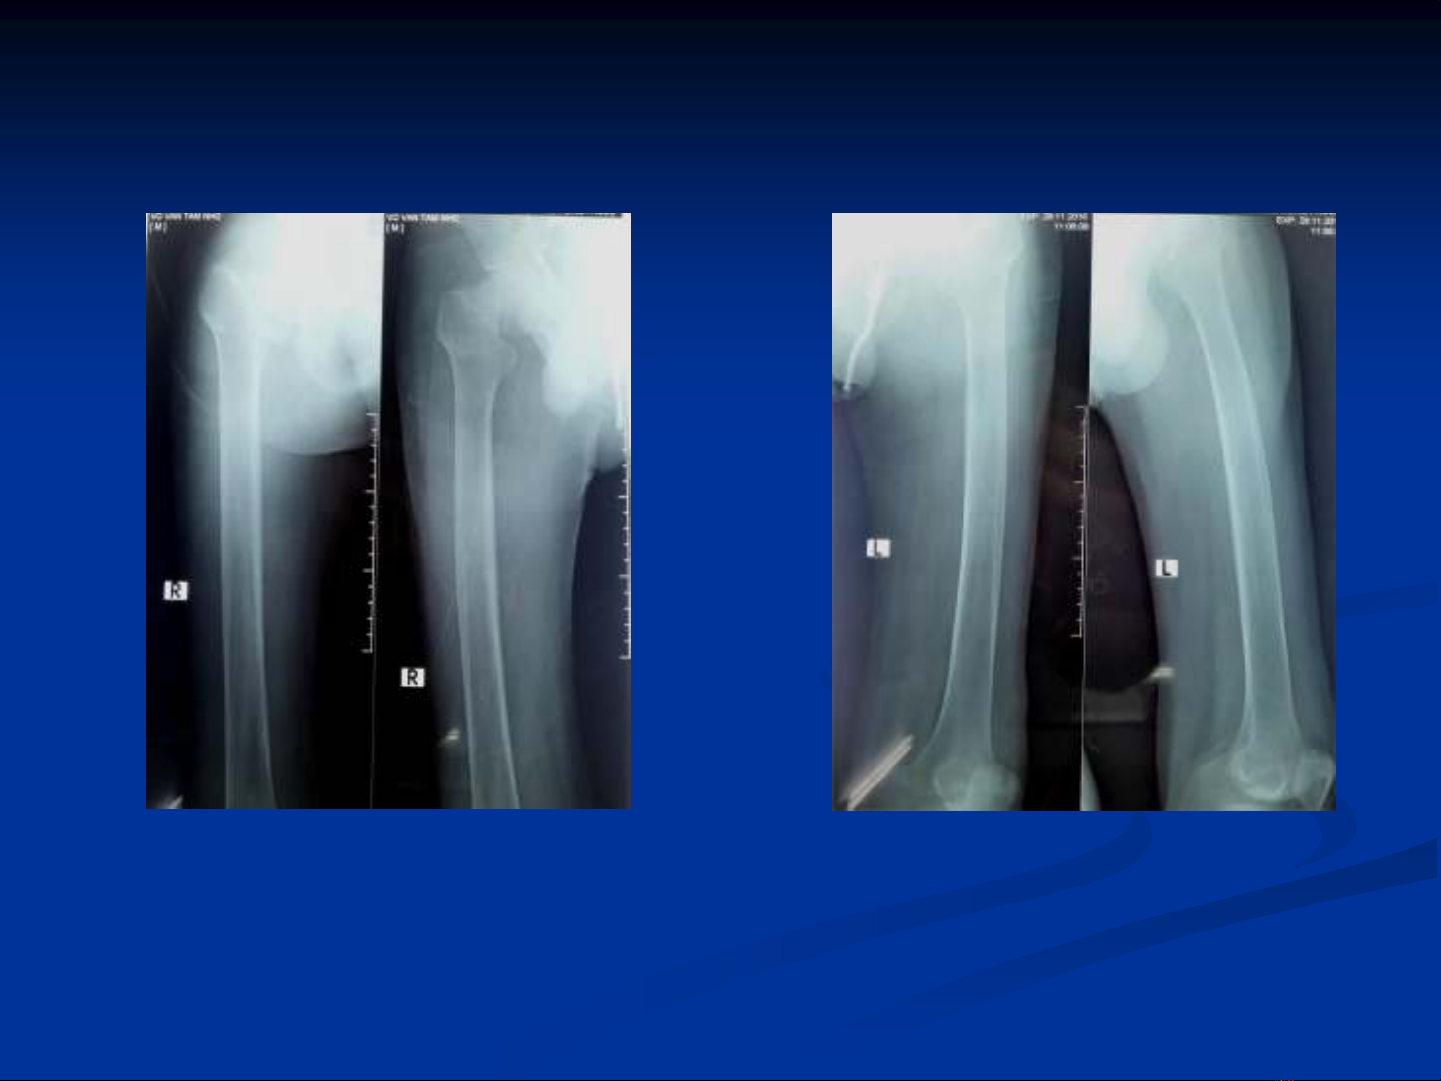

Gãy cổ xương đùi hai bên:

Hình X quang chụp ở bệnh viện bạn-chỉ tập trung vào thân xương đùi